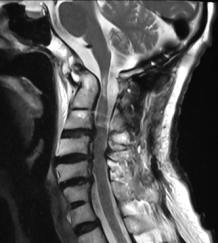

术后,陈阿婆的肢体麻木感显著减轻,精细运动能力也逐步恢复。影像学检查结果显示,陈阿婆的椎管直径增加了超过一倍。得益于细致的术后护理和系统的康复训练,术后两个月返院复查,陈阿婆已恢复独自行走,双手灵活性也大大提升,生活质量显著提高。

术后寰枢关节复位,椎管通畅